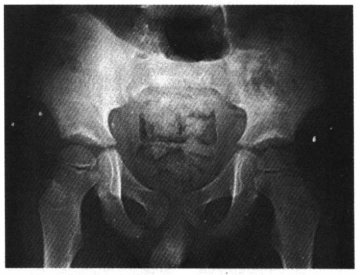

5.小儿的髋关节诸骨,因软骨较厚,关节腔显得较宽,各骨间距离亦较远,所以有时很难肯定是否为髋关节脱臼,尤其在投照时,若两下肢的位置不对称,一侧稍外旋,股骨显得较短,可能误认为脱臼,申通线可不规整(图5)。

图5 小儿右髋关节,略外旋位,申通线可不规整,不要误认为半脱位